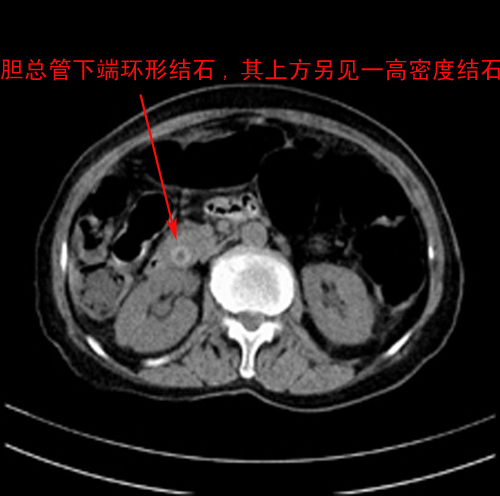

患者,女,75岁。腹痛,体黄5日,膝胸位时腹痛缓解。肝功能明日出来。彩超提示胆总管占位,未见血流信号。心电图提示s-t段改变。患者体质较弱,未能增强。

胆总管上段,腔内有软组织密度影 ,ct值36-44hu。大家看有没有胆管癌的可能。

环形结石

胆管癌并结石。